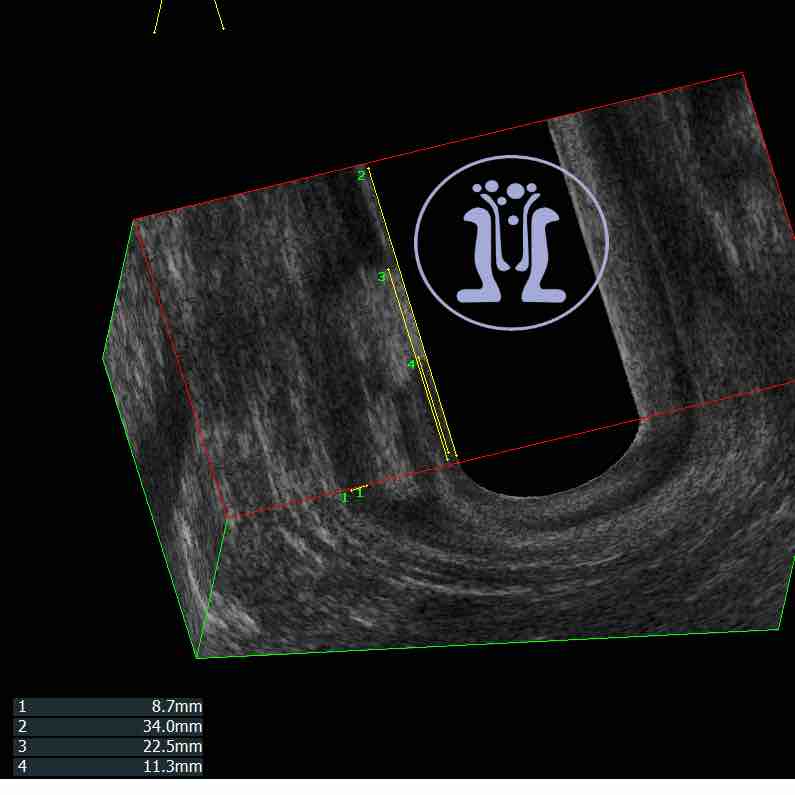

Ενας χειρουργός, μας ζητησε την βοήθεια του για την θεραπεία ενός εμφανούς και απλού συριγγίου σε εύσωμο άνδρα ασθενής 42 ετών. Κάναμε την χαρτογραφηση των σφιγκτήρων και του συριγγίου και καθοδηγήσαμε τον συνάδελφο για την σωστή θεραπεία της περίπτωσης.